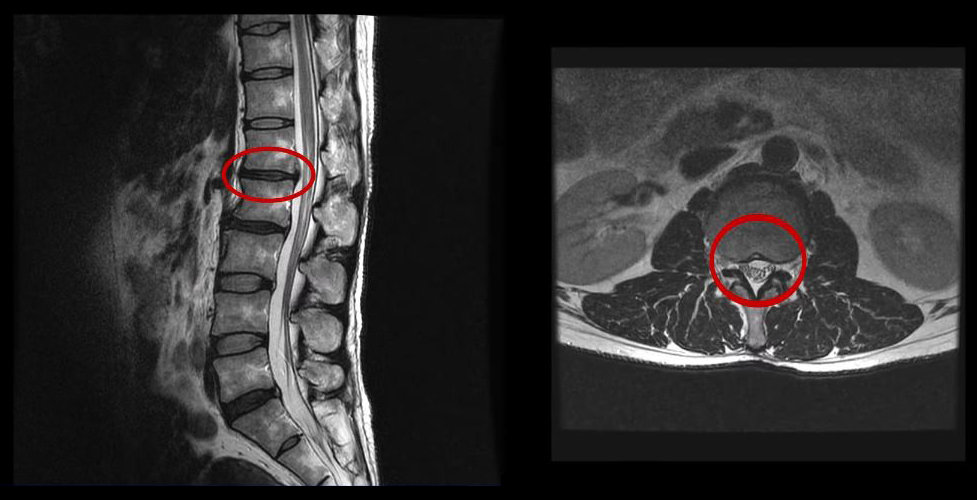

그런데 이 환자분의 MRI를 보면 여러 마디에 퇴행성디스크가 있습니다.

이 환자분은 MRI상으로 거의 대부분 마디의 디스크가 퇴행되고 수핵이 밀려나와 있으며, 정상적인 허리 마디는 4-5번 하나 정도입니다. 그렇기 때문에 MRI만 보면 아마 대부분의 병원에서 허리디스크탈출 또는 퇴행성디스크로 인한 허리통증 및 다리통증으로 진단하고 치료할 것입니다. 이분도 그래서 20년간 그런 치료를 무수히 많이 받았으나 그 어떤 치료도 별 도움이 되지 않았습니다.

이 환자분처럼 오랜 기간 만성적인 허리통증이 있고, 엉덩이가 저리면서 심지어는 양쪽 다리저림까지 있는 환자분들이 많습니다. 그런데 이 환자분의 MRI를 보면 여러 마디의 퇴행성디스크, 디스크탈출, 황색인대의 두꺼워짐, 후관절의 퇴행 등 다양한 병변들을 가지고 있는 걸 볼 수 있는데요. 그렇기 때문에 많은 병원에서 이분을 디스크로 진단하고 거기에 따른 치료가 이루어졌습니다. 그러나 저희가 보기에는 이분의 MRI상으로 보이는 여러 마디의 디스크 문제가 이 환자분이 갖고 있는 증상을 설명할 수 없었습니다.

만성적인 허리통증은 그 원인을 찾기가 매우 힘듭니다. 왜냐하면 만성 허리통증의 대부분은 근육의 기능 문제가 원인인데, 근육의 기능 문제는 MRI상으로는 보이지 않기 때문입니다. 또 양쪽 다리가 저린 이유도 MRI만으로는 알 수 없습니다.